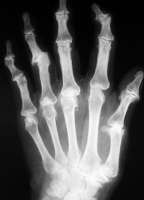

A osteoartrite, também conhecida como doença articular degenerativa, é um processo de deterioração progressiva da cartilagem articular e formação de osso novo (osteófitos) com a superfície articular. A osteoartrose primária está relacionada com a idade e associada a estresse mecânico. A osteoartrite secundária é devido a uma causa subjacente, como trauma, inflamatórias, metabólicas ou a doença do tecido conjuntivo. As características da doença são bem ilustradas nas mãos de adultos com osteoartrose nas figuras abaixo.